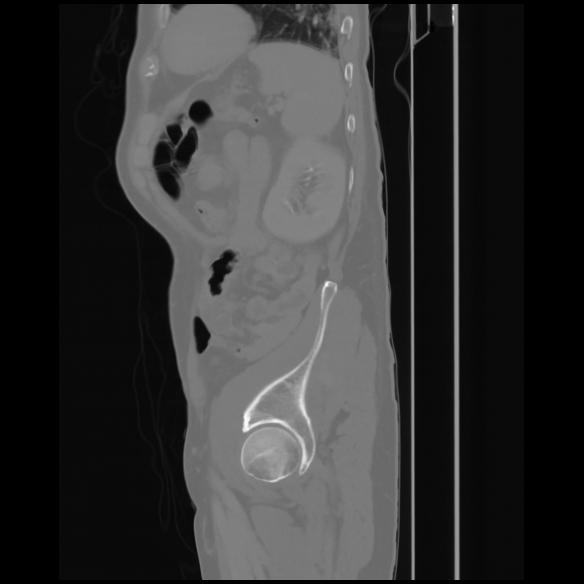

7 CUERPO,CE,Sagittal,3.000,CUERPO,Sagittal,